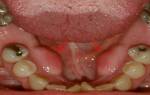

- зубы: наличие кариозных и иных дефектов, не рациональные ортопедические и ортодонтические устройства съемного и несъемного типов способствуют затруднению вымывания слюной микробов, кто приводит к размножению флоры;